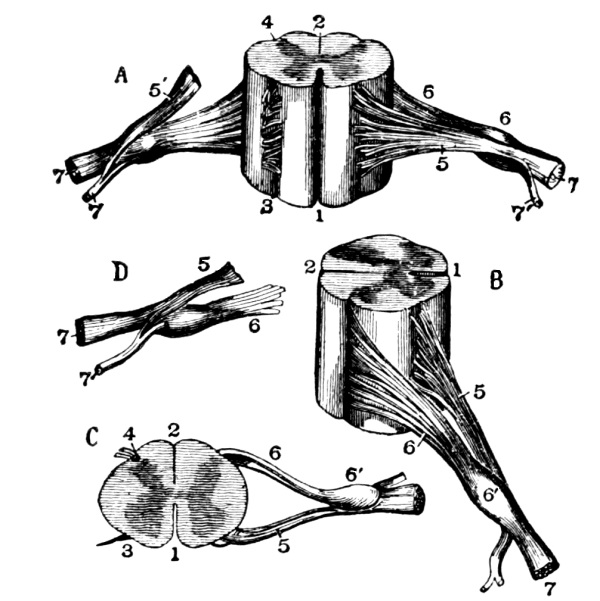

The Cerebrum, 75—The Cerebellum, 78—Pons Variolii, 78—Medulla Oblongata, 78—Spinal Cord, 79—Brain-centers, 81—Motor Tract, 82—Sensory Tract, 82—Reflex Action, 83—Cranial Nerves, 83—Spinal Nerves, 84—Brachial Plexus, 85—Sacral Plexus, 85—The Sympathetic System, 87—The Sympathetic Nerves, 87. |

STRUCTURE AND

FUNCTIONS OF THE BODY.

| The Nervous System | 75 |